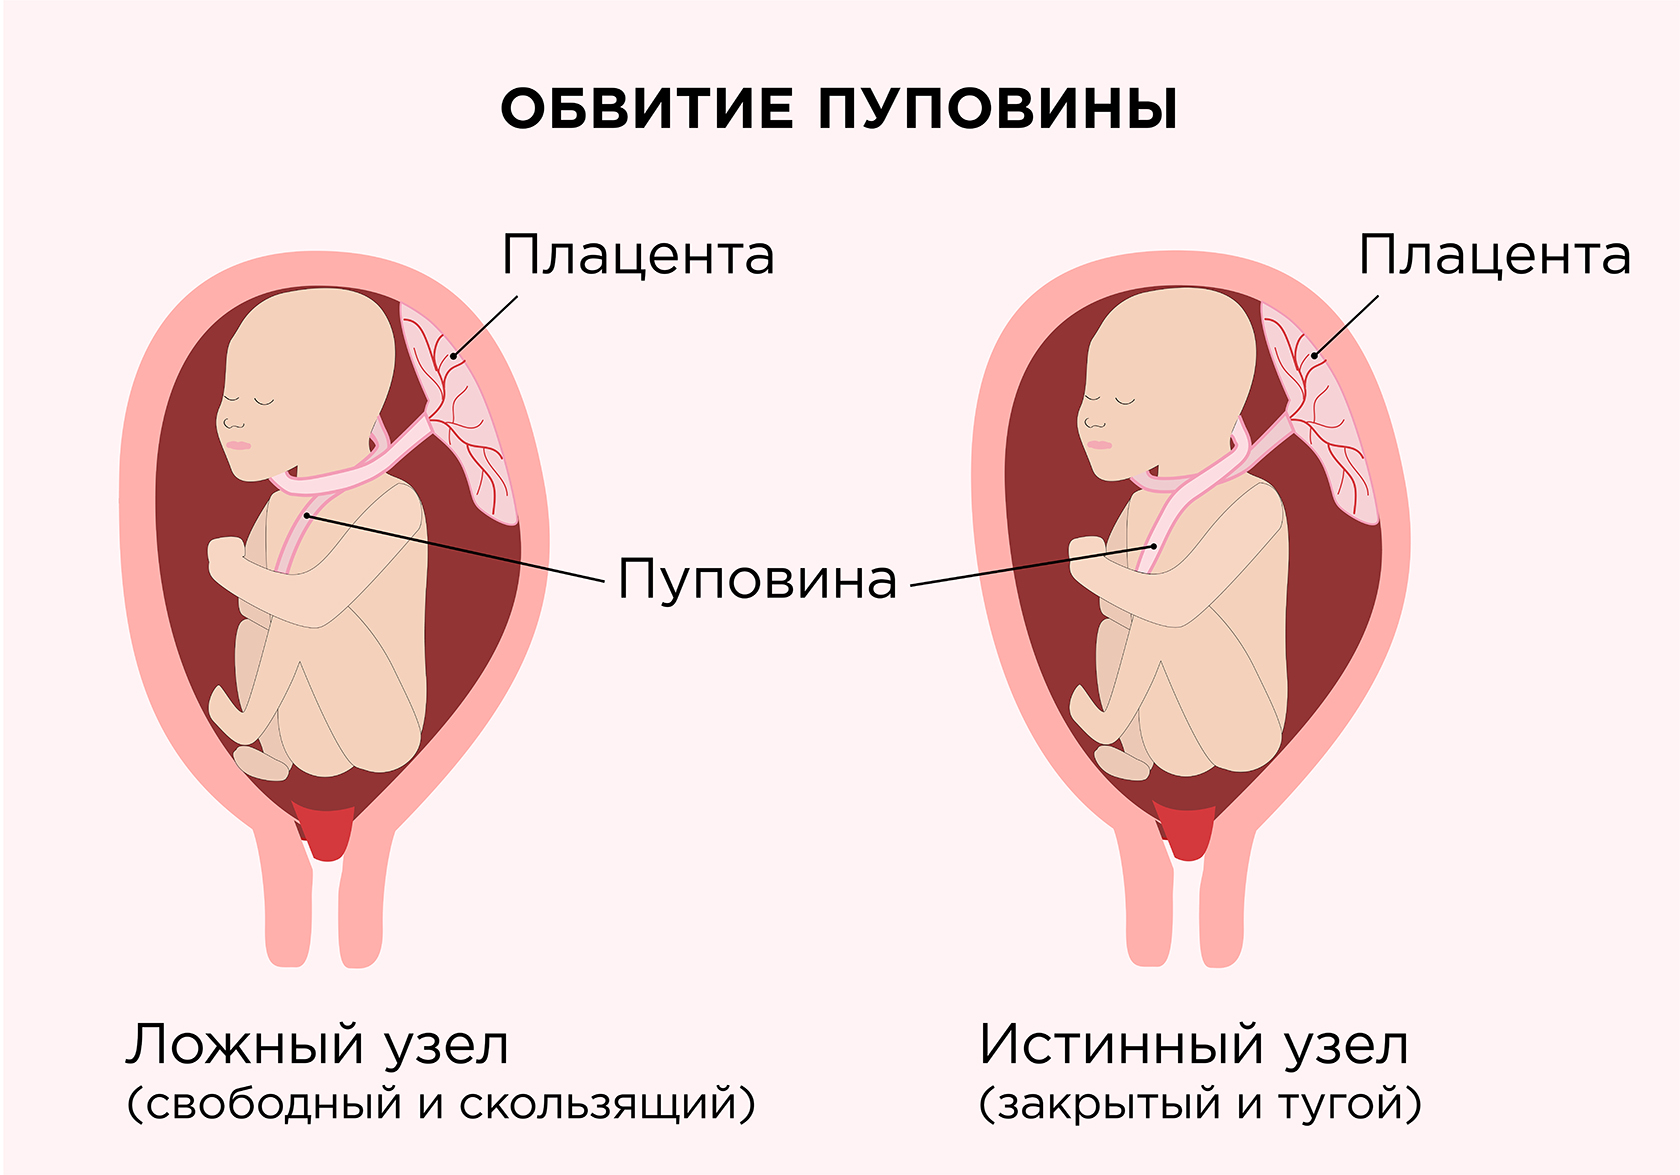

В проекции шеи петля пуповины

Истинный и ложный узел пуповины